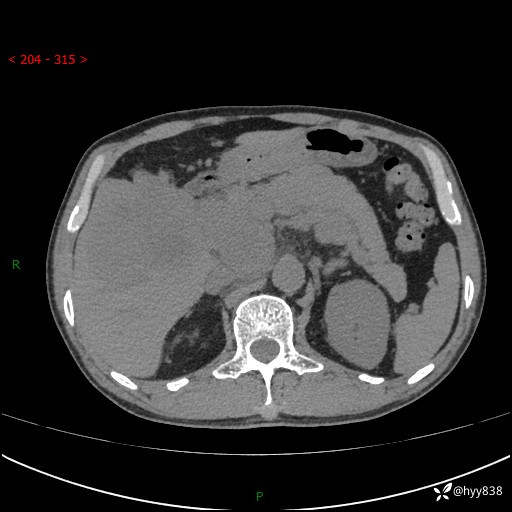

56岁/男,持续性干咳1周余,外院超声发现肝占位,少见病例---结果公布~

现病史:患者1周前无明显诱因出现刺激性干咳,伴食欲减退,无痰,无发热、头晕头痛、恶心呕吐、腹痛腹泻、胸闷喘气、厌油、巩膜黄染等不适,于当地诊所就诊并予以输液治疗,具体不详,患者诉干咳症状稍微好转,现患者为行进一步检查于当地第五人民医院就诊,肝脏彩超提示“肝占位性病变”,遂转入我院门诊就诊,经检查后门诊以“肝占位性病变”收入我科。 患者自起病以来精神、食欲如上述、睡眠一般,大小便正常,近半月内体重降低20余斤,体力无明显下降。

上腹部CT平扫+增强(两期)